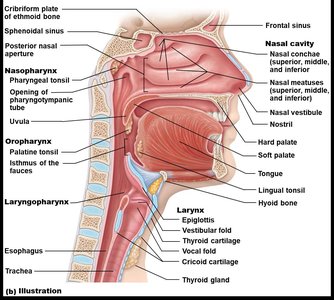

The Pharynx

The pharynx is a muscular tube that serves as a passageway for both air and food, divided into three regions:

Nasopharynx: Lined with pseudostratified ciliated columnar epithelium; contains the uvula and pharyngeal tonsil (adenoids).

Oropharynx: Located behind the mouth; lined with nonkeratinized stratified squamous epithelium; contains palatine and lingual tonsils.

Laryngopharynx: Passageway for food and air; continuous with the esophagus and larynx.

The Larynx

The larynx connects the pharynx to the trachea and is responsible for voice production, maintaining an open airway, and routing air and food using the epiglottis.

Cartilages: Includes thyroid, cricoid, arytenoid, and epiglottis.

Vocal Folds: True and false vocal cords for sound production and airway protection.